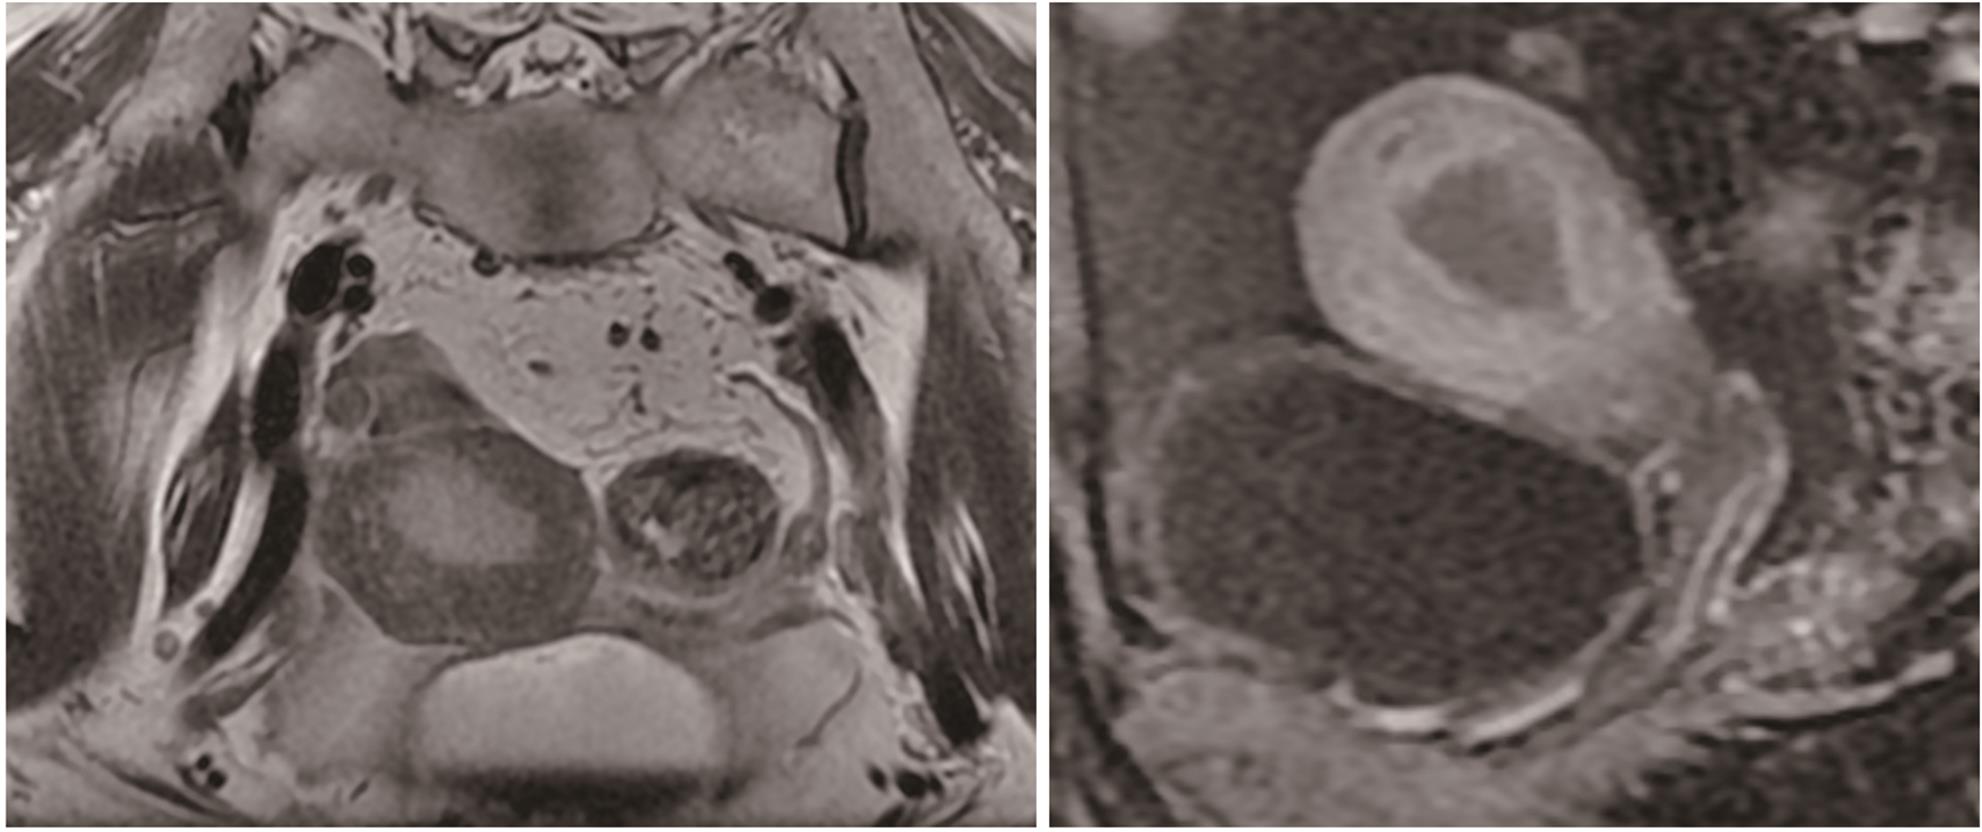

Diagnosis and treatment of decompensated cirrhosis with multiple primary cancers: A case report

2024, 40(9): 1868-1872. DOI: 10.12449/JCH240923

Abstract(927) HTML (392) PDF (1776KB)(108)

Abstract:

Multiple primary cancers (MPC) refer to the presence of more than one type of cancer with different histological features and sites in the same individual, and it is relatively rare in clinical practice. This article reports a case of decompensated cirrhosis with MPC and discusses the diagnosis, treatment, and clinical implications of this patient with decompensated cirrhosis and MPC.